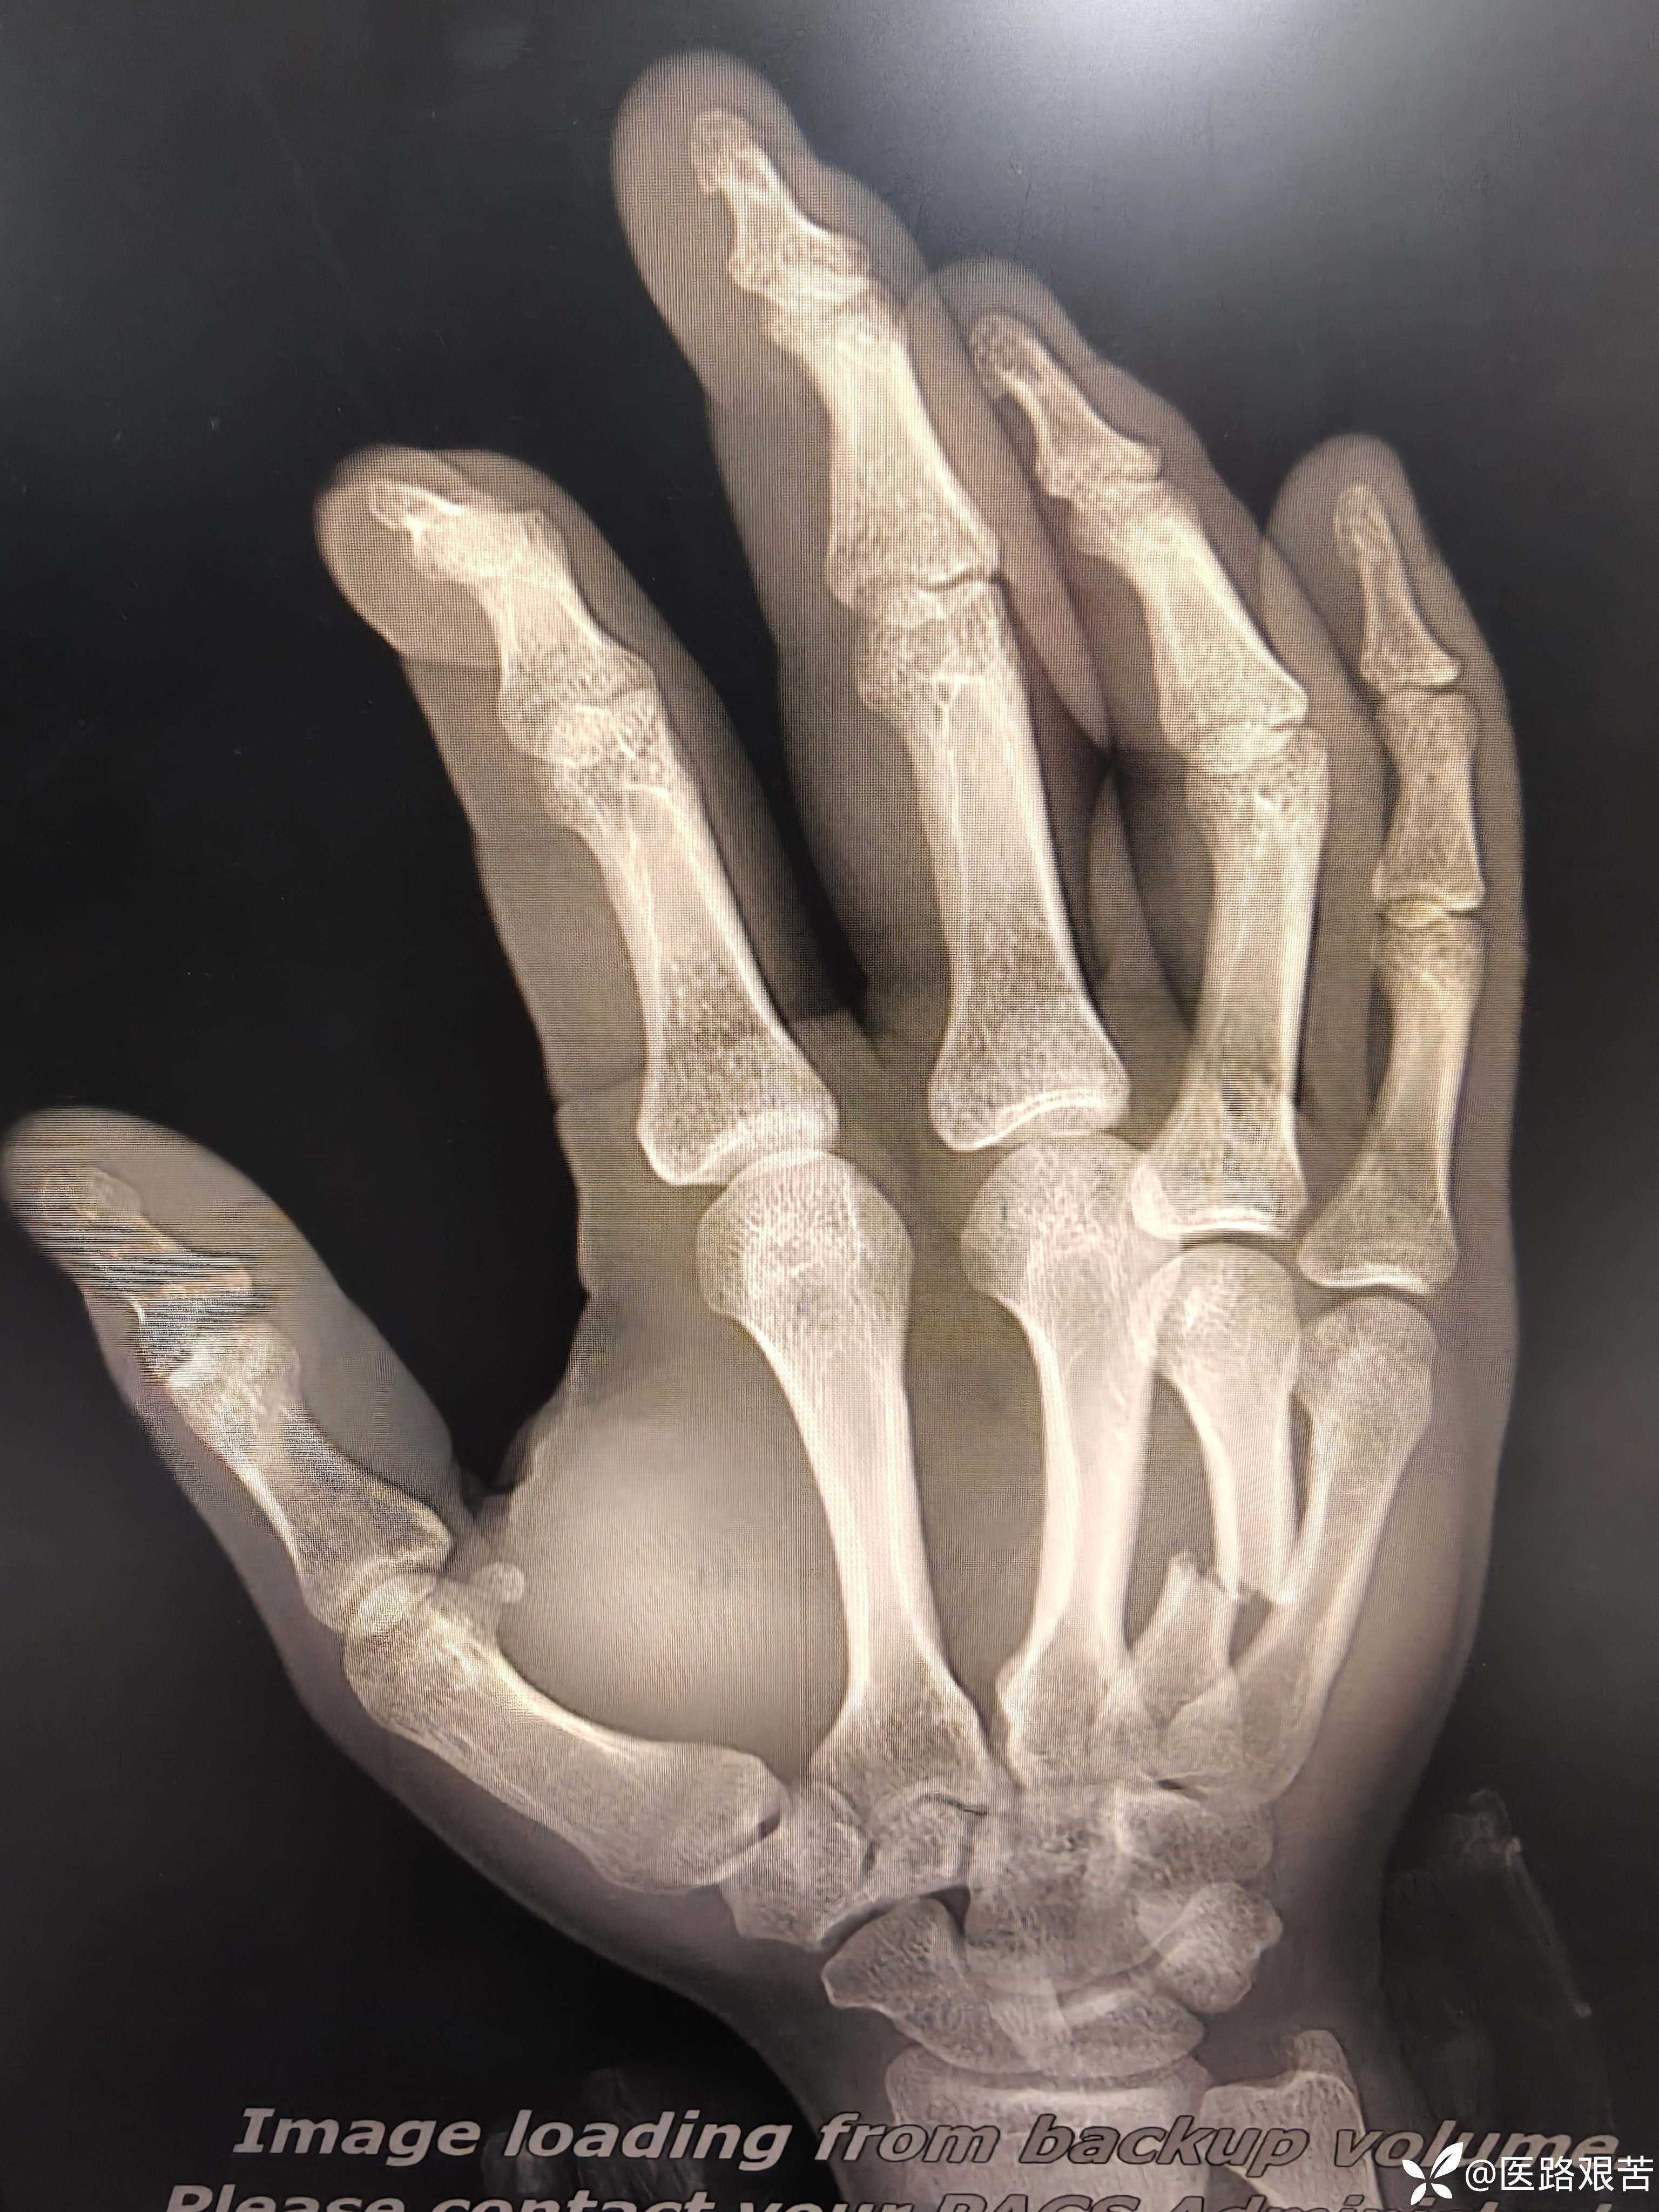

患者,男,32岁,外伤摔倒致右手第四掌骨骨折,伤后1天就医,手法复位石膏固定后,表示骨折立线正,可接受,愈合时间稍长,患者要求解剖复位,并希望早日活动。

术后